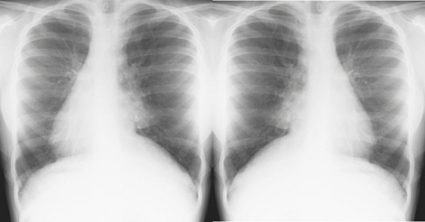

Men den gode Kartagener kom att både sänka och stärka mitt självförtroende tjugo år senare. På barnmottagningen i Lycksele hade jag en treårig pojke från Storuman med envisa svåra förkylningar. Han växte visserligen bra och ökade i vikt som han skulle men var ofta hostig, hängig och infekterad. Jag fann inget särskilt vid min undersökning men remitterade till slut för en lungröntgen, kanske under lite tryck från mamman. Den visade som jag väntat inget speciellt på preliminärutlåtandet. Jag höll på att ge de vanliga goda råden till pojkens mamma när röntgenläkaren kom inrusande. Han bad att omedelbart få tala enskilt med mig.

»Killen har situs inversus!«

Min förmåga till fysikalisk diagnostik sköts i sank med två ord. Jag hade ju lyssnat på honom utan att höra att hjärtat låg på höger sida. Men luftvägsinfektionerna fick plötsligt en dramatisk förklaring, och våra initiala diagnostiska misstag behöll vi för oss själva fram till nu.

Vid Afzelius’ syndrom blir hjärtats läge slumpmässigt, vilket stämmer med att fullständigt situs inversus förekommer hos bara ungefär hälften av patienterna med primär ciliedyskinesi.